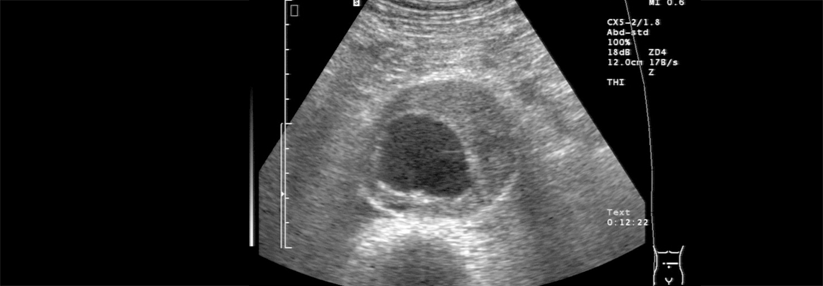

Aortenaneurysmen werden bei Frauen häufiger als bei Männern mittels offener OP repariert, die Sterberate nach endovaskulärer Behandlung ist bei Patientinnen zudem deutlich höher. Wie lassen sich diese Geschlechterunterschiede erklären?

Die Forscher untersuchten retrospektiv mehr als 16 000 Behandelte über 65 Jahre, bei denen zwischen 2003 und 2015 ein Aortenaneurysma versorgt worden war. Rund 12 000 davon waren Männer. Die Frauen waren im Schnitt etwas älter, sie rauchten häufiger und wiesen kleinere Aneurysmen auf.